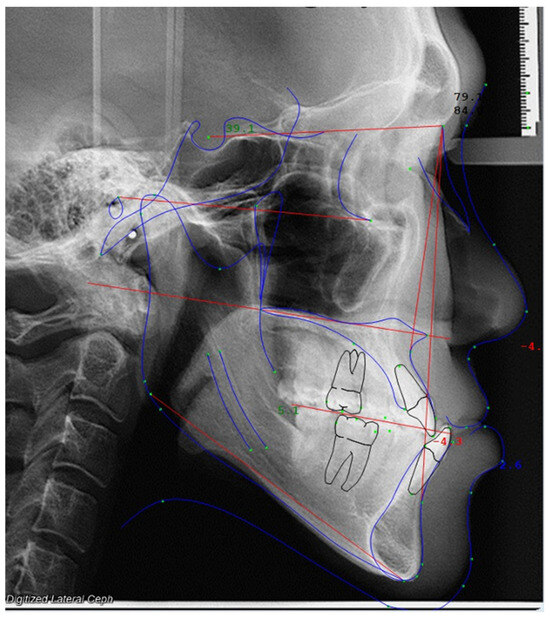

2.2. Cephalometric Analysis

| Landmark | Definition |

|---|---|

| 1. Soft tissue glabella (G’) | Most prominent point in the sagittal plane between the supraorbital ridges. |

| 2. Soft tissue nasion (N’) | Deepest part of the soft tissue outlines in front of the nasion. |

| 3. Pronasale (P) | Tip of the nose. |

| 4. Subnasale (Sn’) | Junction of the nasal septum and upper lip in the mid-sagittal plane. |

| 5. Sella (S) | Geometric center of the pituitary fossa (sella turcica). |

| 6. A-point (A) | Deepest point on the maxilla below the ANS. |

| 7. B-point (B) | Most posterior point on the bony curve of the mandible above the pogonion. |

| 8. Labialis superior (Ls) | Most anterior point on the outline of the upper lip (vermillion border). |

| 9. Labialis inferior (Li) | Most anterior point on the outline of the lower lip (vermillion border). |

| 10. Stomium superior (Stms) | Lowest midline point on the outline of the upper lip (vermillion border). |

| 11. Stomium inferior (Stmi) | Highest midline point on the outline of the lower lip (vermillion border). |

| 12. Soft tissue pogonion (Pog’) | Most anterior point on the outline of the soft tissue chin. |

| 13. Soft tissue menton (Me’) | Lowest point on the outline of the soft tissue chin. |

| 14. Porion (Po) | Top of the external auditory meatus. |

| 15. Orbitale (Or) | Inferior border of orbit. |

| 16. Nasion (N) | Midpoint of the frontonasal sutures in the midsagittal plane. |

| 17. Anterior nasal spine (ANS) | Anterior point of the maxilla at the base of the nose. |

| 18. Posterior nasal spine (PNS) | Posterior point of the bony hard palate. |

| 19. Gonion (Go) | Most posterior and inferior point on the outline of the angle of the mandible. |

| 20. Gnathion (Gn) | Most anterior and inferior point on the bony chin. |

| 21. Menton (Me) | Lowest point on the symphysis of the mandible. |

| 22. Pogonion (Pog) | Most anterior point on the contour of the bony chin in the midsagittal plane. |